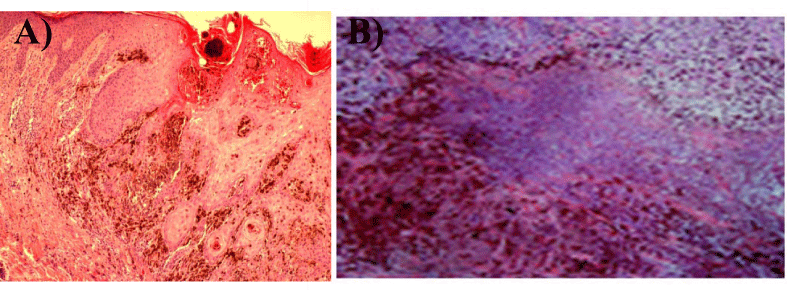

| Figure 2: The histopathology of the primary site of the cutaneous melanoma of patient # 8: (A) Prior to intralesional biotherapy from the biopsy site, and (B) One week after intralesional therapy from the resected tissue of the same patient. Note the massive tumor necrosis and the abundant pigmented histiocytes. (H&E X400). |